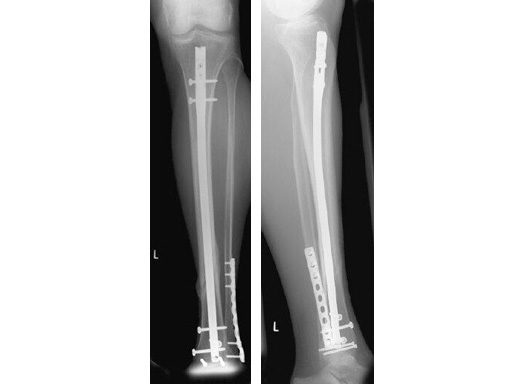

64-year-old woman with an open distal tibial fracture extending into the pilon treated with ETNS.